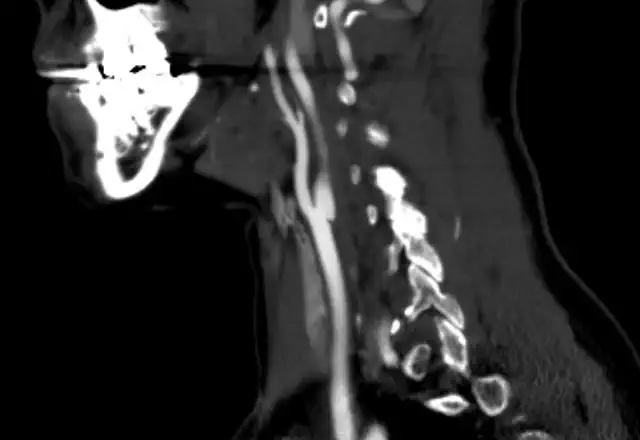

Abdominal aortic aneurysms or AAA are the most common. Most are infra-renal. A thoracic aneurysm is the second most common location.

An infra-renal location means they are in the portion between the renal arteries and the iliac bifurcation. When the abdominal aorta diameter exceeds 3 cm it is considered an aneurysm. In the thoracic aorta the cutoff is 4 cm. The reason for the differential cutoff in aortic diameter is that the normal diameter for the thoracic aorta is larger than for the abdominal aorta.

Other imaging studies used are computed tomography with contrast material and when needed CTA (computed tomography angiography) and magnetic resonance angiography (MRA). Having said that, the “gold standard” for aortic aneurysm imaging is still contrast-angiography. Often before a definitive decision is made regarding treatment, a patient will have to undergo formal angiography.